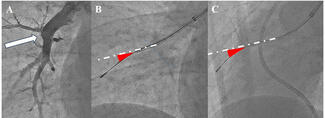

Catheter Positioning

Once the Berman catheter is advanced close to pulmonary capillary wedge position in the lung of interest, the distal balloon is deflated and the central lumen is flushed. During deep inspiration and breath hold by the patient, the catheter position is optimized to allow for small movement of the catheter tip with each heart beat (approximately 1-2 cm of migration during each beat). If the catheter is advanced too deeply, then the tip will appear immobile during the cardiac cycle and indicate positioning within surrounding thromboembolic material or a small-caliber PA segment (Figure 5). Manual or high-pressure contrast injection in this position risks iatrogenic vessel injury. However, if the catheter is not advanced sufficiently, the tip and proximal segment will swing widely during the cardiac cycle. High-pressure contrast injection in this position may cause the catheter to straighten and “kick” back to the main PA segment, resulting in unwanted contrast reflux into the contralateral lung and insufficient vessel filling in the lung being imaged (Figure 6). The optimal position for the Berman tip is within the descending PA distal to the lower-lobe superior segment (ie, within the basal trunk), which allows for simultaneous opacification of the middle and lower-lobe vessels, quickly followed by backfilling of upper-lobe vessels. The vasculature of these middle and lower lobes typically bears greater disease and is of higher clinical interest during angiography. In instances of lower-lobe occlusion, the catheter tip is advanced in the same manner, allowing for some catheter tip migration during a breath hold, but consequently in a more proximal and less deeply seated position (Figures 7 and 8).